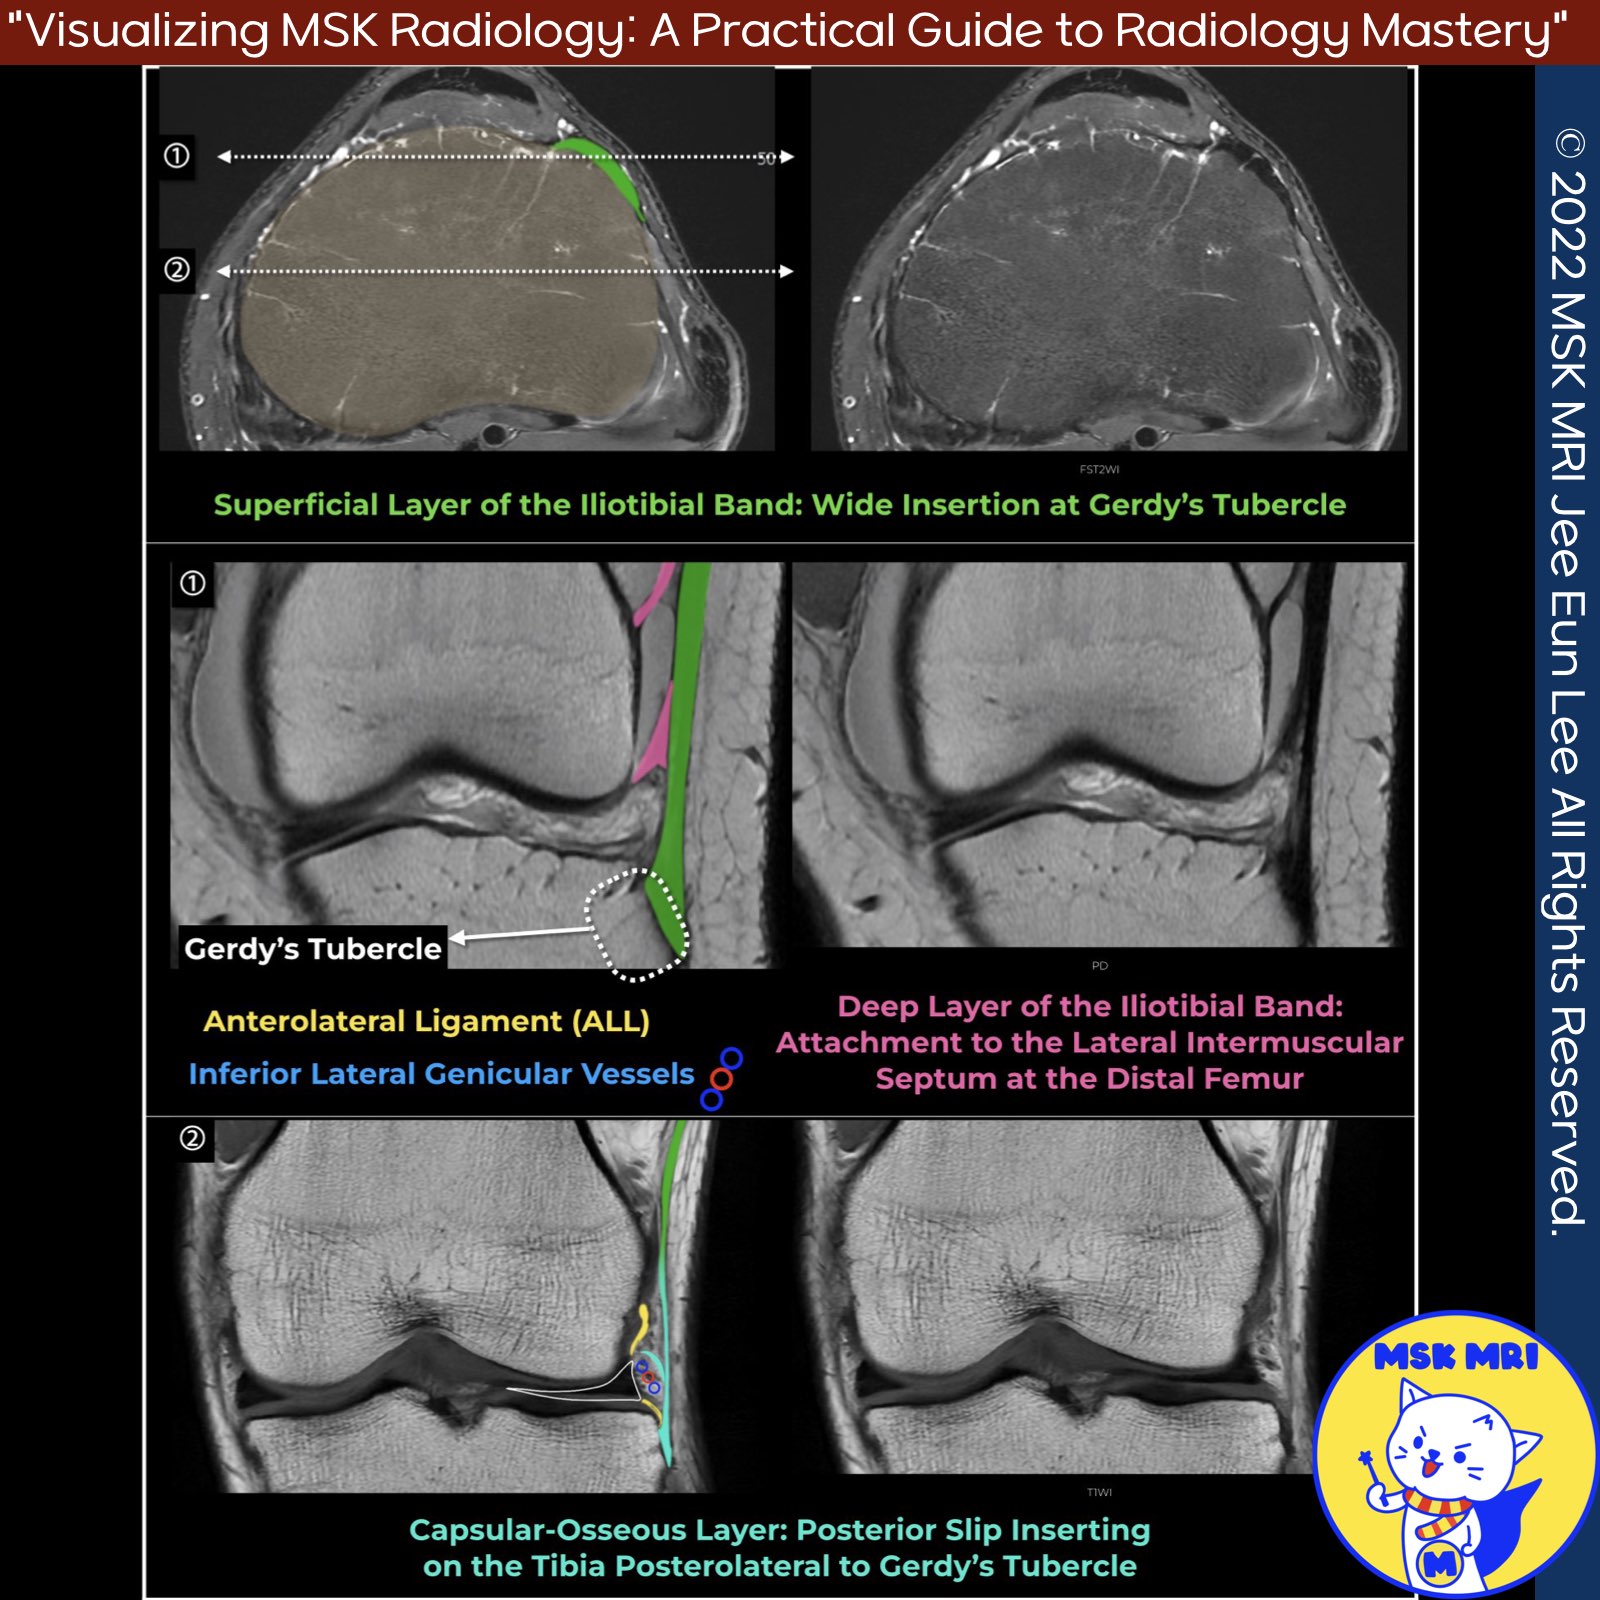

📌 Iliotibial Band Anatomy

- The iliotibial band (ITB or IT band) is a thick band of fascia along the lateral aspect of the thigh, representing a thickening of the fascia lata.

Distal Insertions

- At least 5 distal insertions have been described around the lateral knee, attaching to the distal femur, patella, proximal tibia, and joint capsule.

✅Superficial Layer

- Main tendinous component

- Inserts onto Gerdy's tubercle on anterior lateral tibia

✅Deep Layer

- Attaches superficial layer to lateral supracondylar tubercle of femur

- Blends into intermuscular septum at distal femur

✅Capsulo-Osseous Layer

- Situated deep and posterior to deep layer

- Forms a sling over lateral femoral condyle

- Inserts onto tibial tuberosity posterior and proximal to Gerdy's tubercle

- Some consider it the same as the anterolateral ligament